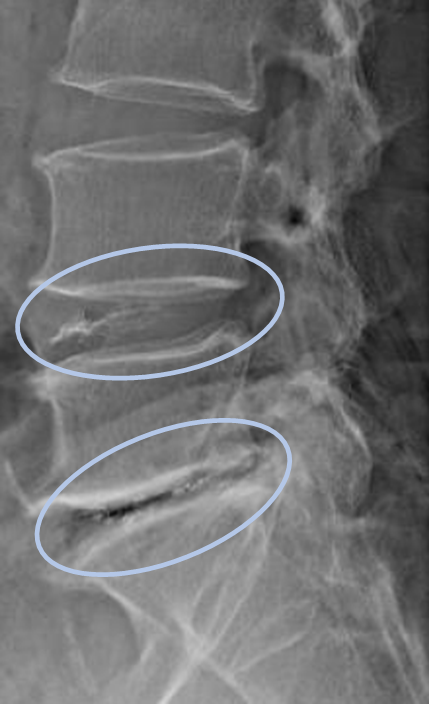

画像及び所見について

- L4/5,5/s-椎間板変性

- L4/5-椎間板ヘルニア

以上の事が画像上認められます。

・L4/5-椎椎間板ヘルニアを認め、主症状の原因の可能性が高い

・L5/s-椎間板変性による椎間孔狭窄を認め、主症状の原因の可能性がある